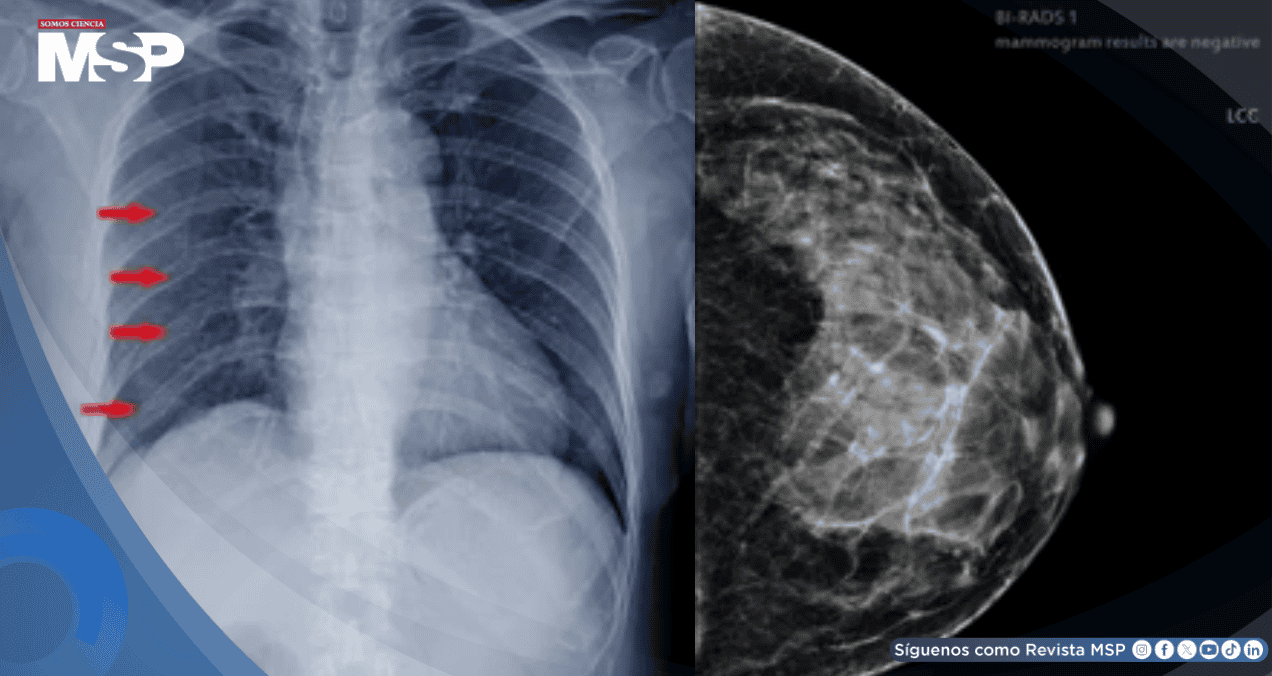

Dos años después de completar ese segundo tratamiento, la paciente comenzó a sufrir un dolor intenso y opresión en el pecho. Los estudios de imagen, como la tomografía computarizada, revelaron múltiples fracturas en las costillas del lado izquierdo.

Estas fracturas no se debían a metástasis (extensión del cáncer), sino a un efecto tardío de la radiación. Los huesos, debilitados por la radioterapia previa y la reirradiación, habían desarrollado osteorradionecrosis, perdiendo su capacidad de curarse adecuadamente.